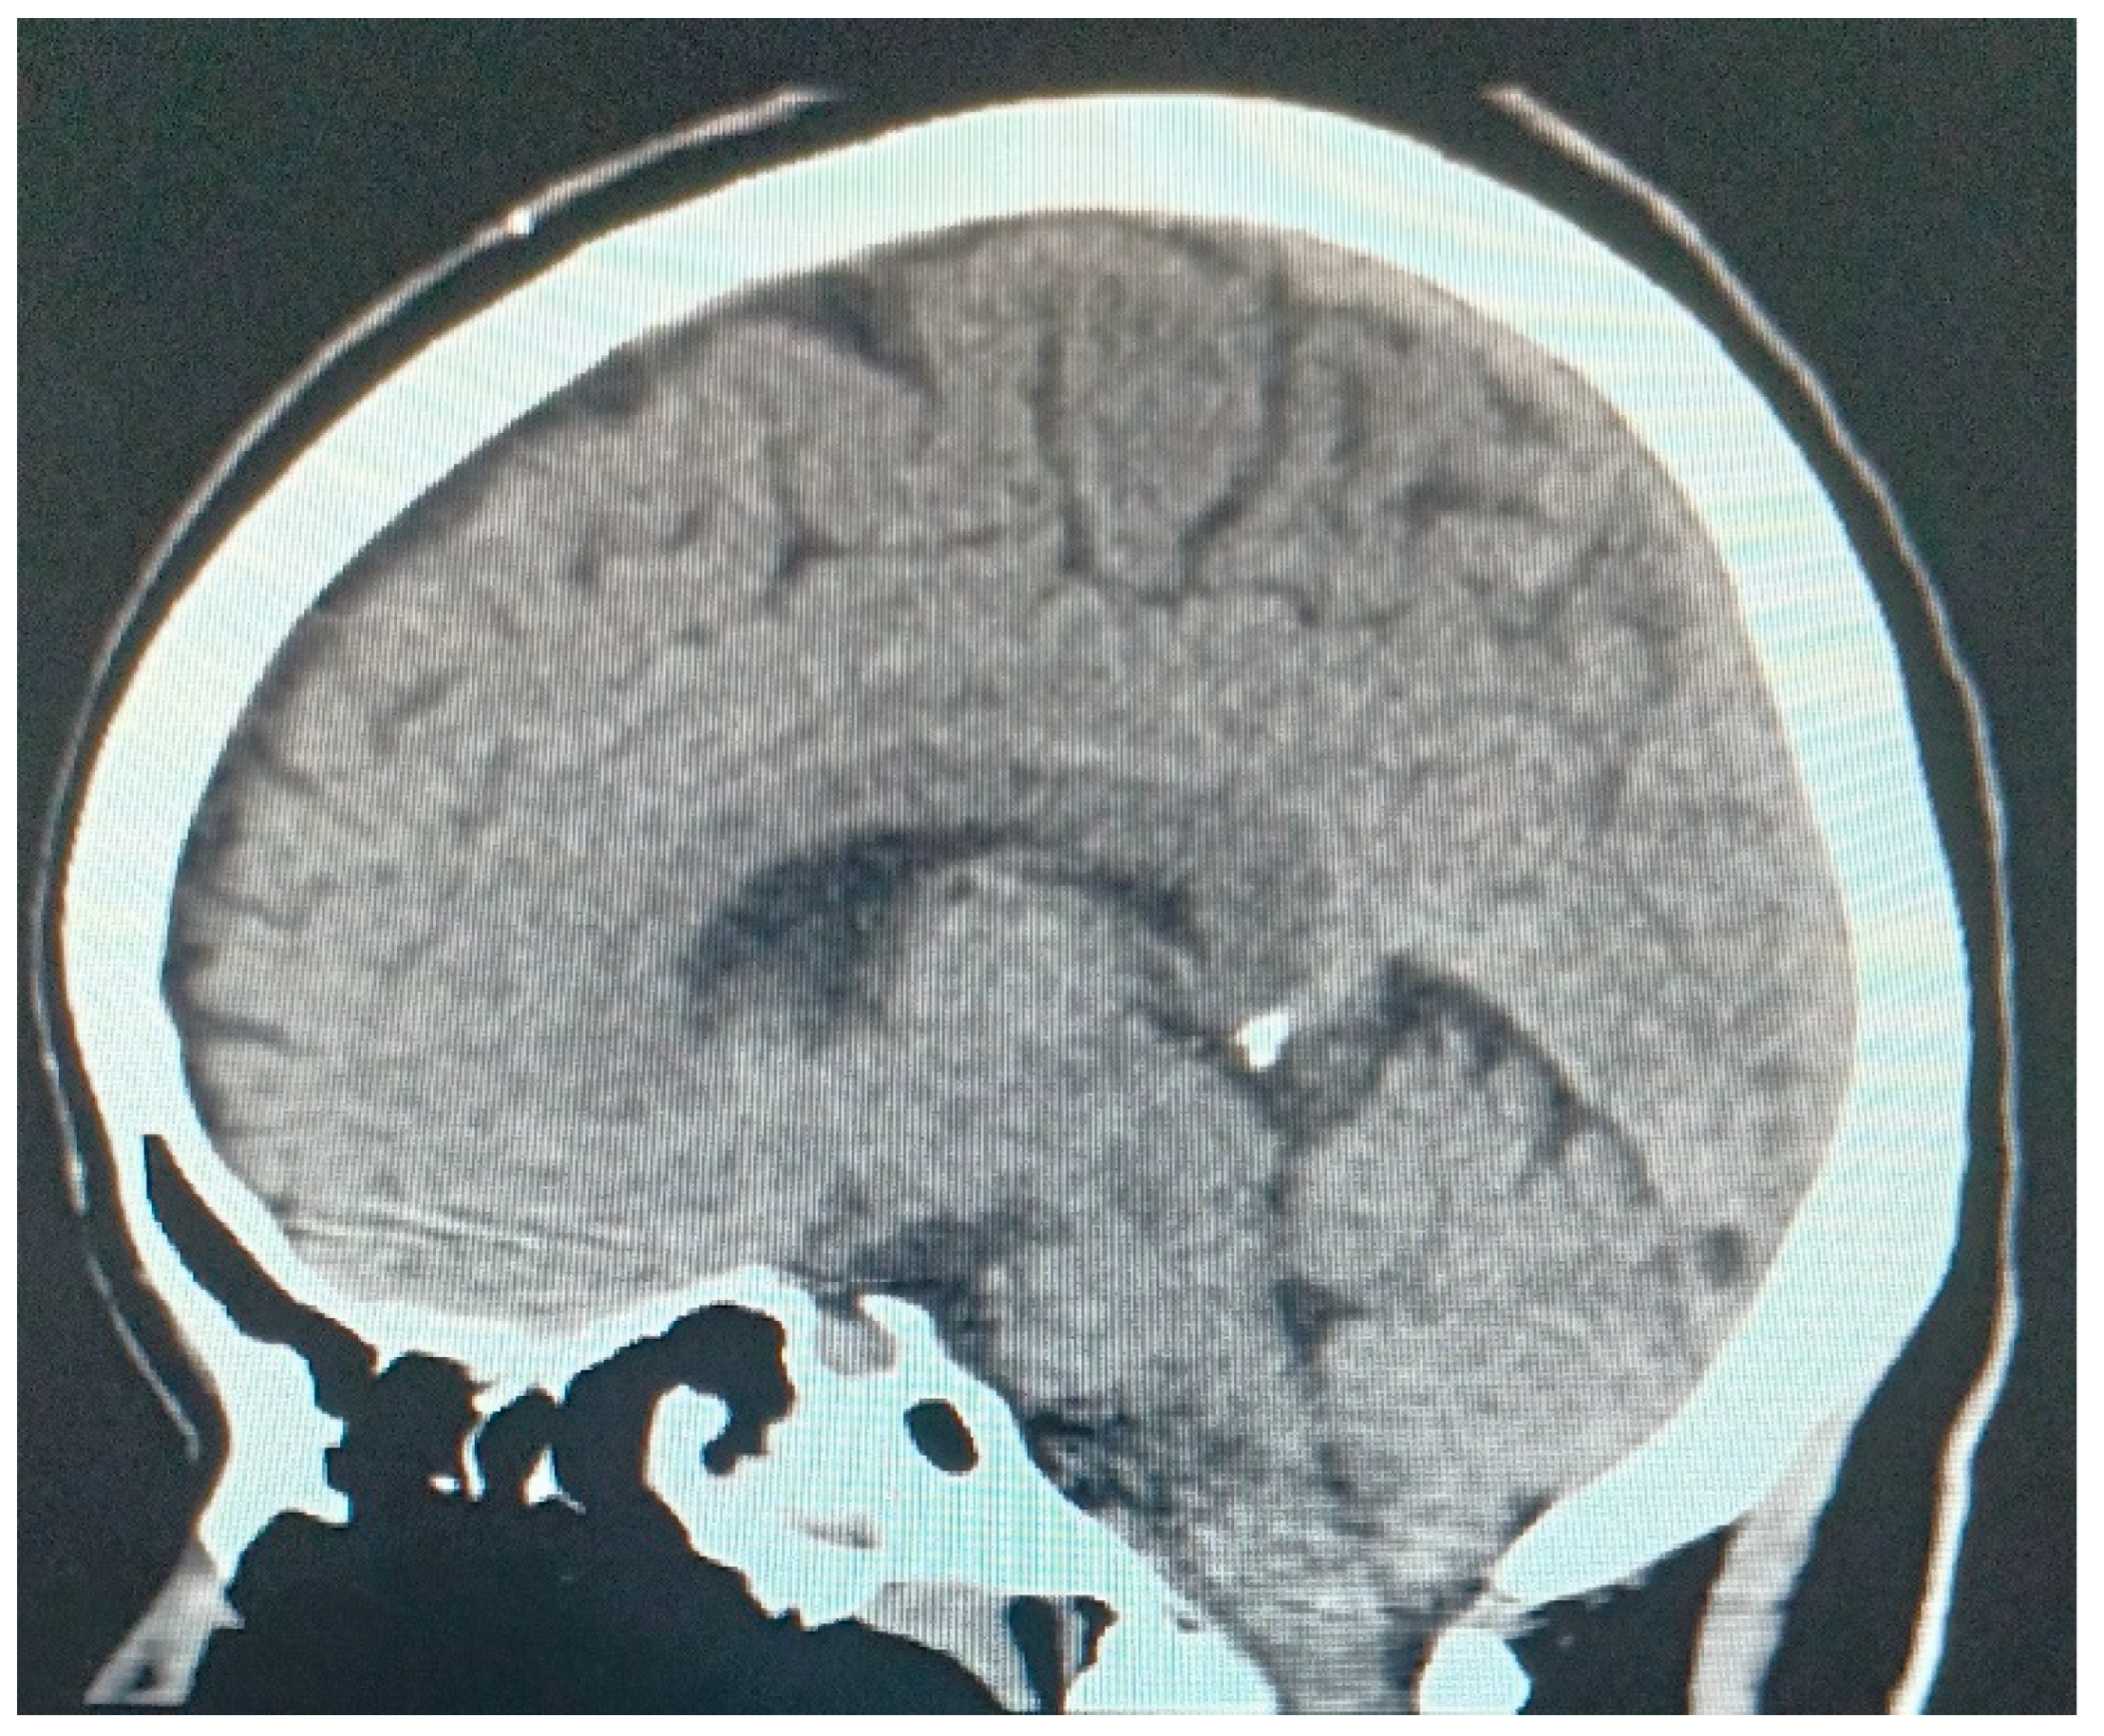

- Simple and contrast-enhanced computed tomography is an examination that can help in the diagnosis in the acute phase between a hemorrhagic or ischemic vascular lesion (Figure 1).